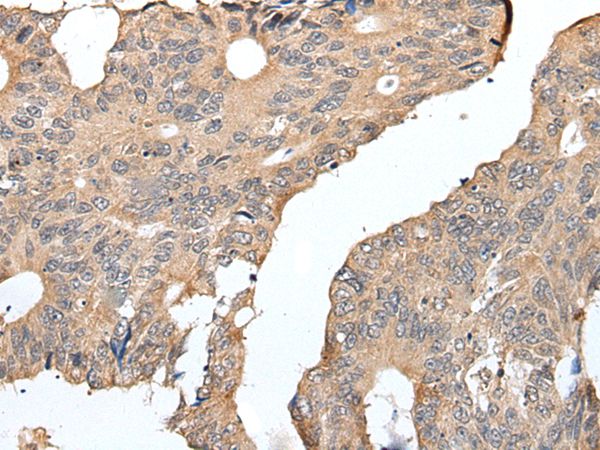

The image on the left is immunohistochemistry of paraffin-embedded Human colorectal cancer tissue using SEPW1 Antibody at dilution 1/25, on the right is treated with synthetic peptide. (Original magnification: x200)